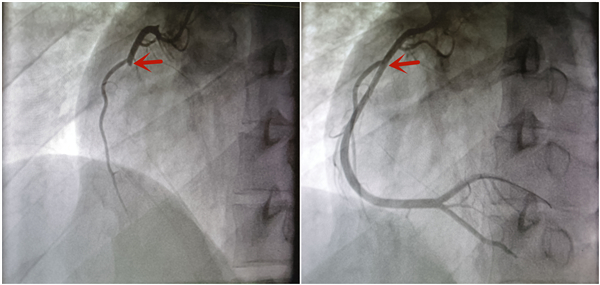

醫生做介入手術開通血管。通訊員餘宇提供

這次,小鄧在當地醫院得到確診,但當地無法做急診介入手術,在進行溶栓處理後,他被送到武漢亞洲心臟病醫院做進一步救治。經急診冠脈造影檢查發現,小鄧的右冠狀動脈中段完全閉塞。醫生透過介入手術開通了閉塞的血管,並做了藥物球囊擴張術。小鄧目前已經脫離危險。